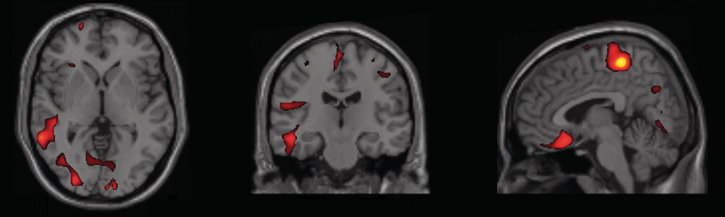

Parálisis supranuclear progresiva (PSP)

Ouede causar desequilibro, dificultades en la marcha y una tendencia de caerse para atrás. También restringe los movimientos de los ojos, que pueden llevar a tener dificultades para leer, caídas mientras se bajan escaleras y visión borrosa o doble o alta sensibilidad a la luz. También se produce el cierre involuntario de los párpados, llamado blefaroespasmo, cambios en la memoria y el comportamiento, en las emociones o las motivaciones y problemas en el habla y al tragar.